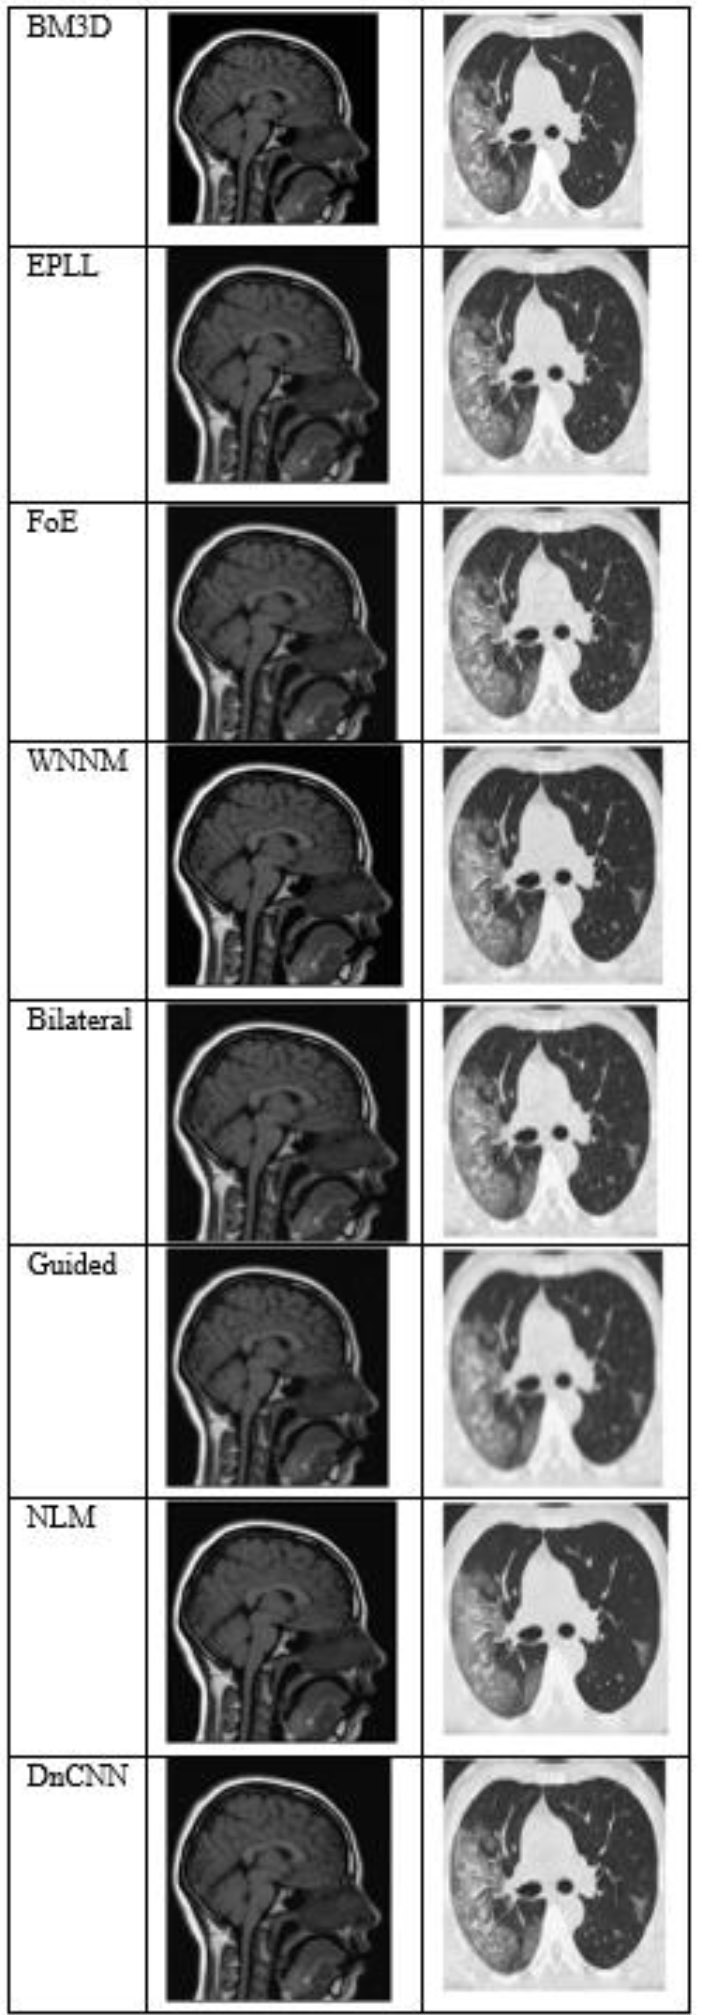

Fig. (4) shows the results at a noise variance of 0.01, where it has been observed that all algorithms produce clear images, except for the Guided algorithm.

The output of different algorithms at a noise variance of 0.01.